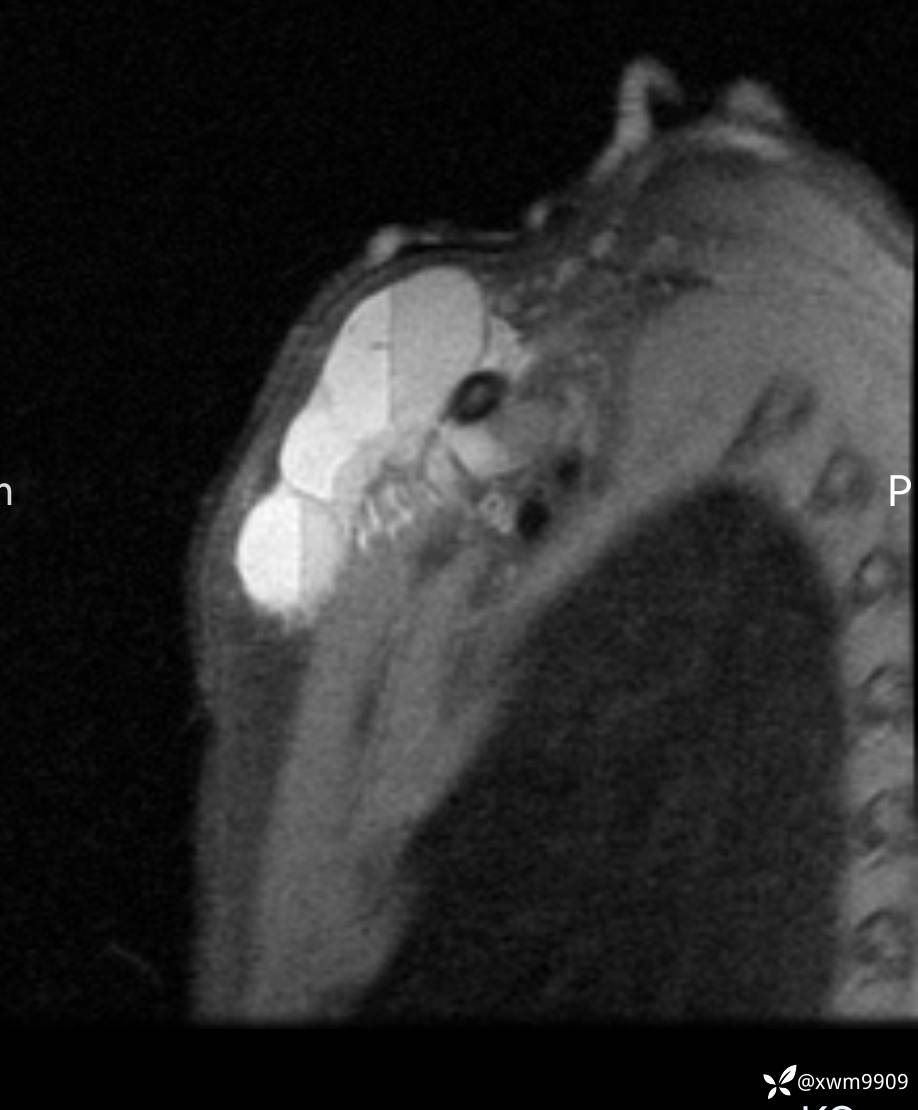

2024-03-19,门诊“摔伤右锁骨肿胀疼痛6小时。拟“锁骨骨折”要求摄:右肩关节正侧位,右锁骨轴位检查。

2024-03-20,女,6岁。因“发现右侧胸部肿物伴疼痛1天”入院。

2、现病史:家属代诉昨日洗澡时发现右胸肿物,压痛明显,查DR:未见明显异常,自行予云南白药,症状稍好转。临床拟:锁骨周围血肿收入院。

3、查体,右锁下方可及一约5x6Cm肿物,软丶边清丶未见明显发红,肤温不高,压痛明显,不可推动,稍有波动感。其他无特殊。

CT:

2、CT、MR肿块内可见液-液平面,常见有哪些疾病。